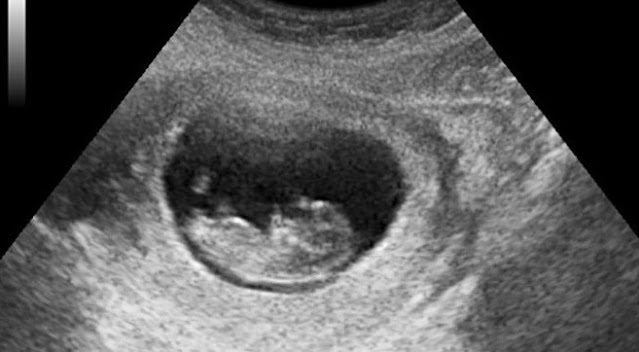

Az orvosok természetes azonnal elvégeztek rajta mindenféle vizsgálatot, többek között az ultrahangvizsgálatot is. Ekkor olyasmit találtak, amitől tátva maradt a szájuk, és amit alig akartak elhinni.

Ugyanis a kislány éppen vajúdott… És nem ez volt az egyetlen sokkoló dolog az egészben, hanem az, hogy senki sem vette észre, hogy egyáltalán terhes.